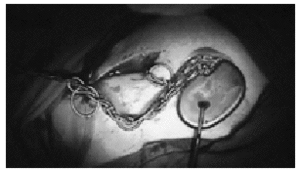

El primer caso se presentó en una mujer de 72 años, con deterioro intelectual moderado por demencia senil e intervenida de bypass aortocoronario años atrás. La paciente ingresó por presentar enfermedad del seno sintomática y se implantó un marcapasos DDDR. Las radiografías y los seguimientos posteriores al implante fueron normales. Dos meses tras el alta, la enferma acudió a consulta por no tar estimulación pectoral derecha. En la radiografía (fig. 1) se observaba un "trenzado de ambos cables" en un eje vertical, con desplazamiento de los electrodos hasta la vecindad del pectoral derecho. La paciente reconocía haber manipulado el generador. Se recolocaron los cables (fig. 2) y el generador se suturó a la fascia del pectoral.

Figura 2. Fotografía tomada en el momento de recolocar el marcapasos en la que se observa la "trenza" que han formado los cables por rotar el generador en su eje vertical.